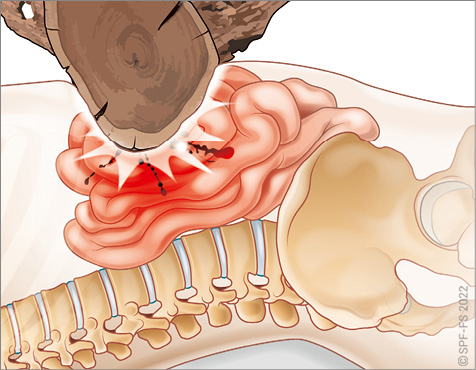

Le bassin

Le bassin osseux (ou pelvis) constitue la jonction entre la colonne vertébrale et les membres inférieurs. En forme d'entonnoir, plus large chez la femme que chez l'homme, il est composé par :

Figure 2-11 : les os du bassin